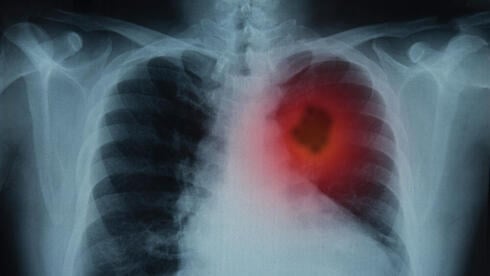

Patritumab Deruxtecan Application Withdrawn for EGFR-Mutated Lung Cancer

Merck and Daiichi Sankyo have voluntarily withdrawn their Biologics License Application for patritumab deruxtecan for treating EGFR-mutated non-small cell lung cancer after the Phase 3 trial failed to meet overall survival endpoints, despite promising progression-free survival results.